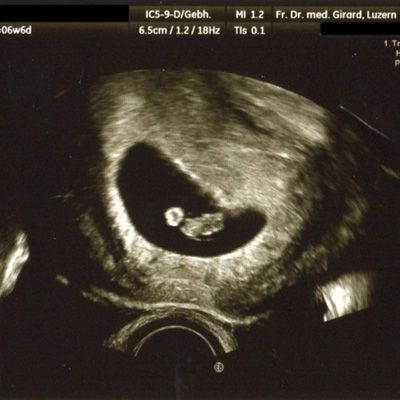

Der Ultraschall hilft uns dabei als einzige Methode, das ungeborene Kind in der Gebärmutter direkt sichtbar zu machen.

können wir die Intaktheit und das Alter der Schwangerschaft feststellen. Diese Information ist von grosser Bedeutung, um beispielsweise in der Spät-Schwangerschaft ein allfälliges vermindertes Wachstum des Kindes erkennen zu können. Auch können Mehrlinge mit hoher Sicherheit erfasst oder ausgeschlossen werden. Zudem kann schon in diesem frühen Alter eine Reihe schwerer Fehlbildungen erkannt werden. Mit der Messung der Nackenhaut-Dicke können Hinweise auf eine mögliche Chromosomen-Störung (beispielsweise das Down-Syndrom = Trisomie 21) erfasst werden.